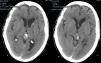

Presentamos el caso de una paciente de 72 años de edad sin antecedentes de interés que consultó en urgencias por un cuadro de 2 semanas de evolución de alteración de la marcha, cefalea y vómitos. El TAC craneal reveló la presencia de hidrocefalia obstructiva secundaria a una lesión pineal con impronta en el tercer ventrículo. La resonancia magnética mostró, además de la lesión ya referida, otra más pequeña situada en el foramen de Lushcka derecho. Se llevó a cabo una ventriculostomía endoscópica del suelo del tercer ventrículo y la biopsia endoscópica de la lesión, cuyo resultado fue de metástasis compatible con carcinoma de pulmón. Se realizó un TAC toracoabdominopélvico que mostró una masa pulmonar compatible con el carcinoma primario. Se decidió tratamiento sistémico de la enfermedad. La paciente falleció 2 meses tras el diagnóstico.

A 72-year-old female with no relevant medical history consulted in the emergency room for a two-week history of headache, vomiting and gait disturbance. Head CT scan revealed obstructive hydrocephalus secondary to a pineal mass with compression of the third ventricle. Magnetic Resonance showed another mass located in the right Lushcka foramen. Endoscopic third-ventriculostomy and biopsy of pineal mass were performed. Pathological analysis was consistent with metastasis of carcinoma. Full-body CT scan showed a lung mass related to primary carcinoma. The patient received systemic treatment for metastatic lung cancer. She died two months after diagnosis.